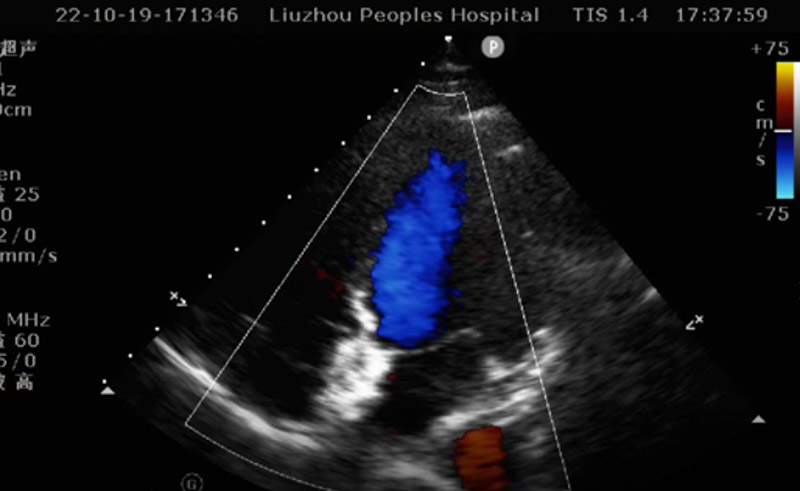

針對韋女士的病情,醫院立即組織了多學科會診,決定行經胸超聲引導經皮卵圓孔未閉封堵手術進行治療。該術式與傳統介入手術相比,避免了X線對患者的放射損傷,對于有懷孕打算的韋女士來講十分合適。

手術如期進行,心臟外科、超聲科團隊共同協作,在超聲引導下順利將封堵傘精準通過卵圓孔未閉處,釋放封堵傘,完美封堵缺口。術后幾日,患者便痊愈出院。